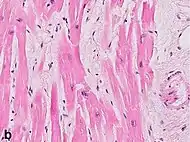

Under the microscope, myocardial infarction presents as a circumscribed area of ischemic, coagulative necrosis (cell death). On gross examination, the infarct is not identifiable within the first 12 hours.[20]

Although earlier changes can be discerned using electron microscopy, one of the earliest changes under a normal microscope are so-called wavy fibers.[21] Subsequently, the myocyte cytoplasm becomes more eosinophilic (pink) and the cells lose their transversal striations, with typical changes and eventually loss of the cell nucleus.[22] The interstitium at the margin of the infarcted area is initially infiltrated with neutrophils, then with lymphocytes and macrophages, who phagocytose ("eat") the myocyte debris. The necrotic area is surrounded and progressively invaded by granulation tissue, which will replace the infarct with a fibrous (collagenous) scar (which are typical steps in wound healing). The interstitial space (the space between cells outside of blood vessels) may be infiltrated with red blood cells.[20]

| Stretched/wavy fibres | 1–2 h |  | ||

| Coagulative necrosis: cytoplasmic hypereosinophilia | 1–3 h | 1–3 days; cytoplasmic hypereosinophilia and loss of striations | > 3 days: disintegration |  |

| Fibroblast and young collagen* | 5–10 days | 2–4 weeks | After 4 weeks; depends on size of infarction; |  |

| Dense fibrosis | 4 weeks | 2–3 months | No |  |